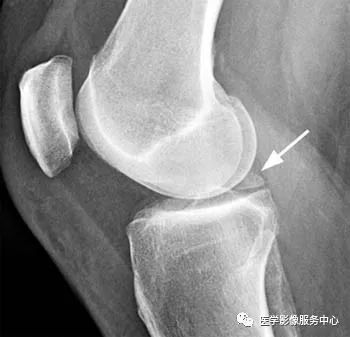

三、半月板小骨

半月板小骨的病因尚不确定,但可能是创伤后或残留的结构,可能无症状或与局部疼痛有关。它们最常见于内侧半月板后角内;在平片上经常被误认为是游离体。在MRI能够显示半月板小骨位于半月板内,并容易误诊为半月板磨损并撕裂。

在T1加权矢状图像上,可见骨化(箭头)位于内侧半月板的后角内;